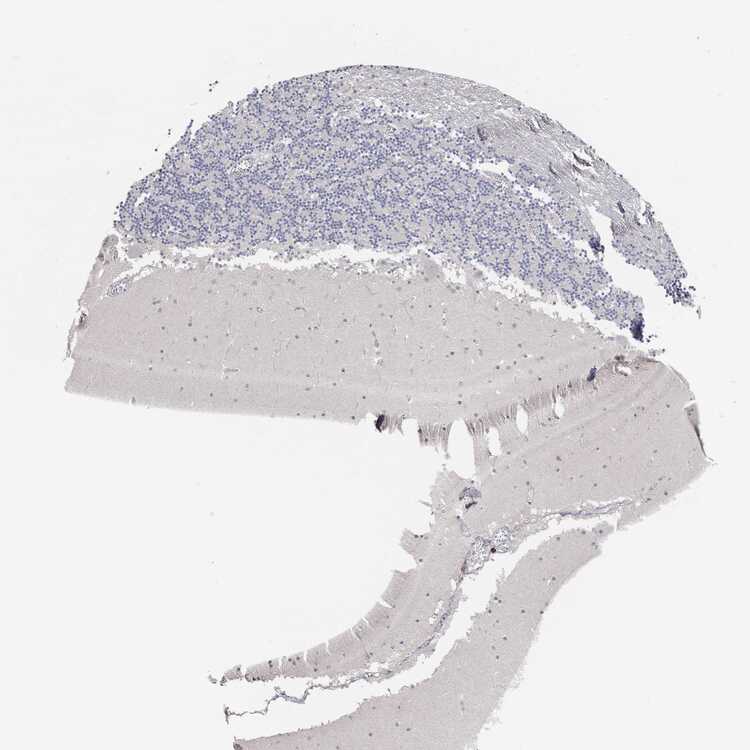

BRAIN CEREBELLUM Show tissue menu

CEREBELLUM - Expression summary

Cells in granular layer: Low

Cells in molecular layer: Low

Purkinje cells: Not detected

CEREBELLUM - Antibody stainingi

Antibody staining in the annotated cell types in the current human tissue is reported as not detected, low, medium, or high, based on conventional immunohistochemistry profiling in selected tissues. This score is based on the combination of the staining intensity and fraction of stained cells.

Each image is clickable and will lead to virtual microscopy that enables deeper exploration of all samples and also displays staining intensity scores, fraction scores and subcellular localization as well as patient and tissue information for each sample.

Purkinje cells Not detectedNot detectedLowHighNot detected

Cells in granular layer Not detectedNot detectedNot detectedNot detectedLow

Cells in molecular layer Not detectedNot detectedNot detectedMediumLow